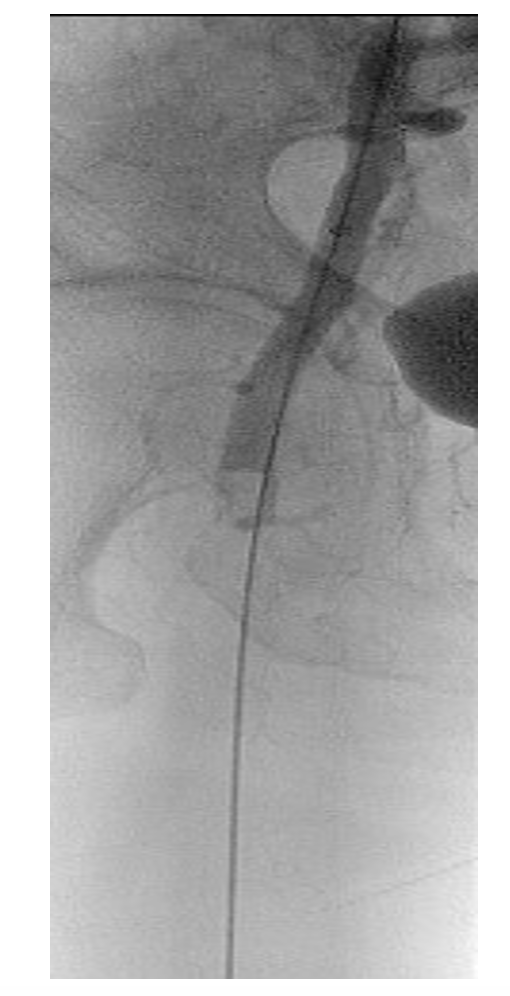

A 6 Fr/90 cm Fortress introducer sheath (Biotronik) was placed at the right subclavian artery (Figure 3). Recanalization was done with a 0.018" Glidewire Advantage (Terumo) and a Trail Blazer Angled Support Catheter (Medtronic) (Figure 4). Balloon dilatations were done with a 2/120 mm Passeo-18 (Biotronik) and a 3/120 mm Passeo-18, without effect (Figure 5). Then, a 0.014" Fielder wire (Asahi) was placed to the palmar arch. Thromboaspiration of red thrombotic masses was done with a 6 Fr Eliminate aspiration catheter (Terumo). Again, there was no distal flow.

A 0.035" Storq wire (Cordis) was then placed in the right radial artery. Effective EVT with a 2.06 mm AngioJet Solent Omni was performed, first in the right brachial artery, then in the axillary artery (Figure 6). The brachial artery was successfully recanalized, but distal embolization in the brachial artery bifurcation occurred again. We repeated EVT with the same 2.06 mm AngioJet Solent Omni in the brachial and radial arteries. Blood flow was restored in the right brachial and radial arteries (Figure 7).